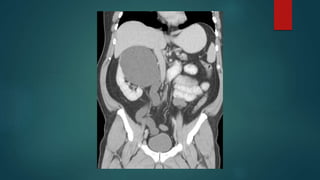

 CT demonstrates a very large

right sided ureteric mass with

trapped contrast, which almost

mimics a vascular aneurysm, and

proximal long

standing hydronephrosis.